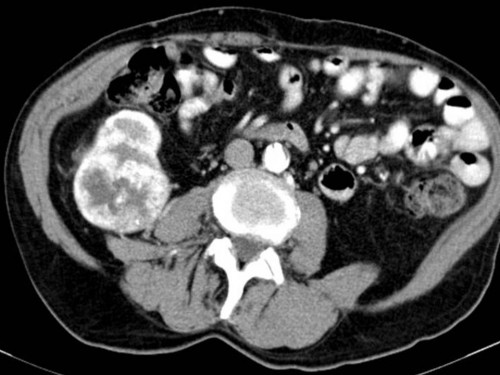

62-jähriger Mann. In der letzten Zeit klagte er immer wieder über Flankenschmerzen. Da er bereits seit Jahren an Lumbalgien leidet, misst er diesen zunächst keine große Bedeutung bei. Vor einer Woche bemerkte er, dass sein Urin rötlich verfärbt ist, weshalb er seinen Hausarzt aufsuchte. Dieser überwies ihn direkt an eine urologische Klinik.